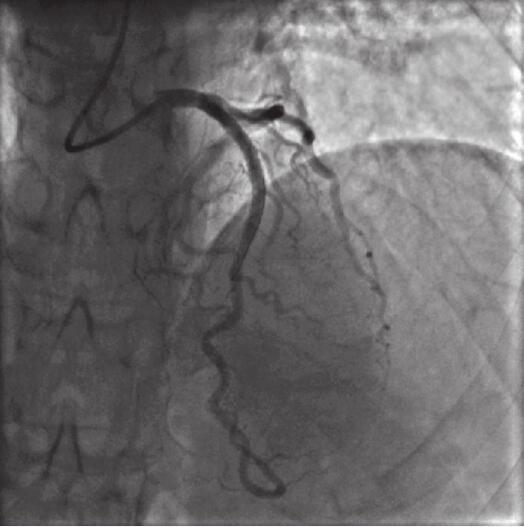

前降支近段病变处经球囊扩张后植入4.0mm×36mm支架1枚,复查造影示支架植入处无残余狭窄,血流TIMI Ⅲ级(图11-5)。

图11-5 降支近段狭窄前降支PCI术后